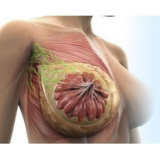

Mamoplastia de Elevação

Se você não sabe onde encontrar bons profissionais, equipe médica compromissada e sempre pronta a atender bem o seu cliente? Pois não se preocupe mais pois a FF Cirurgia Plástica coloca à disposição do cliente a possibilidade de contratar assistência médica pertinente que o possibilite submeter-se à mamoplastia de elevação.

Não pense duas vezes: conheça o consultório médico que realiza mamoplastia de elevação!

Praticidade pensada no que é mais adequado às necessidades do cliente, com profissionais de saúde por perto, levando maior segurança e eficiência até você. Busque com essa equipe todas as informações que precisa e saia satisfeito e tranquilo! Qualidade e bom atendimento você encontra de excelência na FF Cirurgia Plástica.